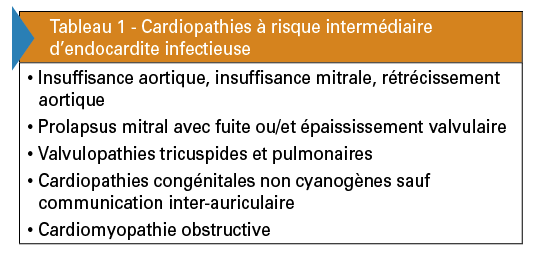

Le risque d’endocardite infectieuse dépend de la cardiopathie sous-jacente, ce qui conduit à distinguer des patients à risque intermédiaire et à risque élevé d’endocardite. Les cardiopathies exposant à un risque intermédiaire d’endocardite sont pour la plupart des valvulopathies natives et des cardiopathies congénitales avec shunt gauche-droit (tableau 1).